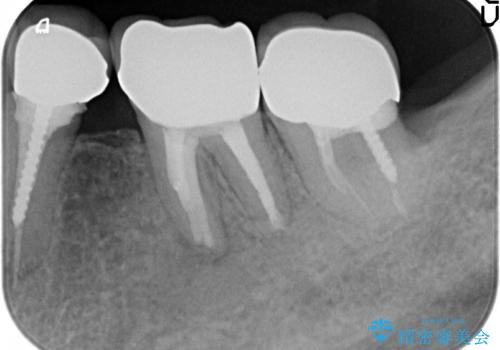

検査の結果左下6に根尖病変を認めたため、再根管治療を行いました。

その後症状の消失を確認し、オールセラミッククラウンによる補綴を行いました。

今回用いたオールセラミッククラウンはジルコニアフレームという白い素材の上にセラミックを盛っているため、審美性が非常に高いのが特徴です。

また、ジルコニアは人工ダイヤモンドの材料にも使われているほど高い強度を持っており、そのためオールセラミッククラウンは審美性だけでなく、奥歯やブリッジの補綴も可能とするクラウンです。